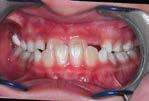

Case treated with EF Classe II Slim

Treatment time: 12 months

Enzo

• Class II 1 • Predisposition to DMD• Skeletal Class II with maxillary proalveolia and mandibular retrognathia

• Lingual dysfunction during swallowing

Before wearing EF Class II Slim

After 12 months wearing EF Class II Slim